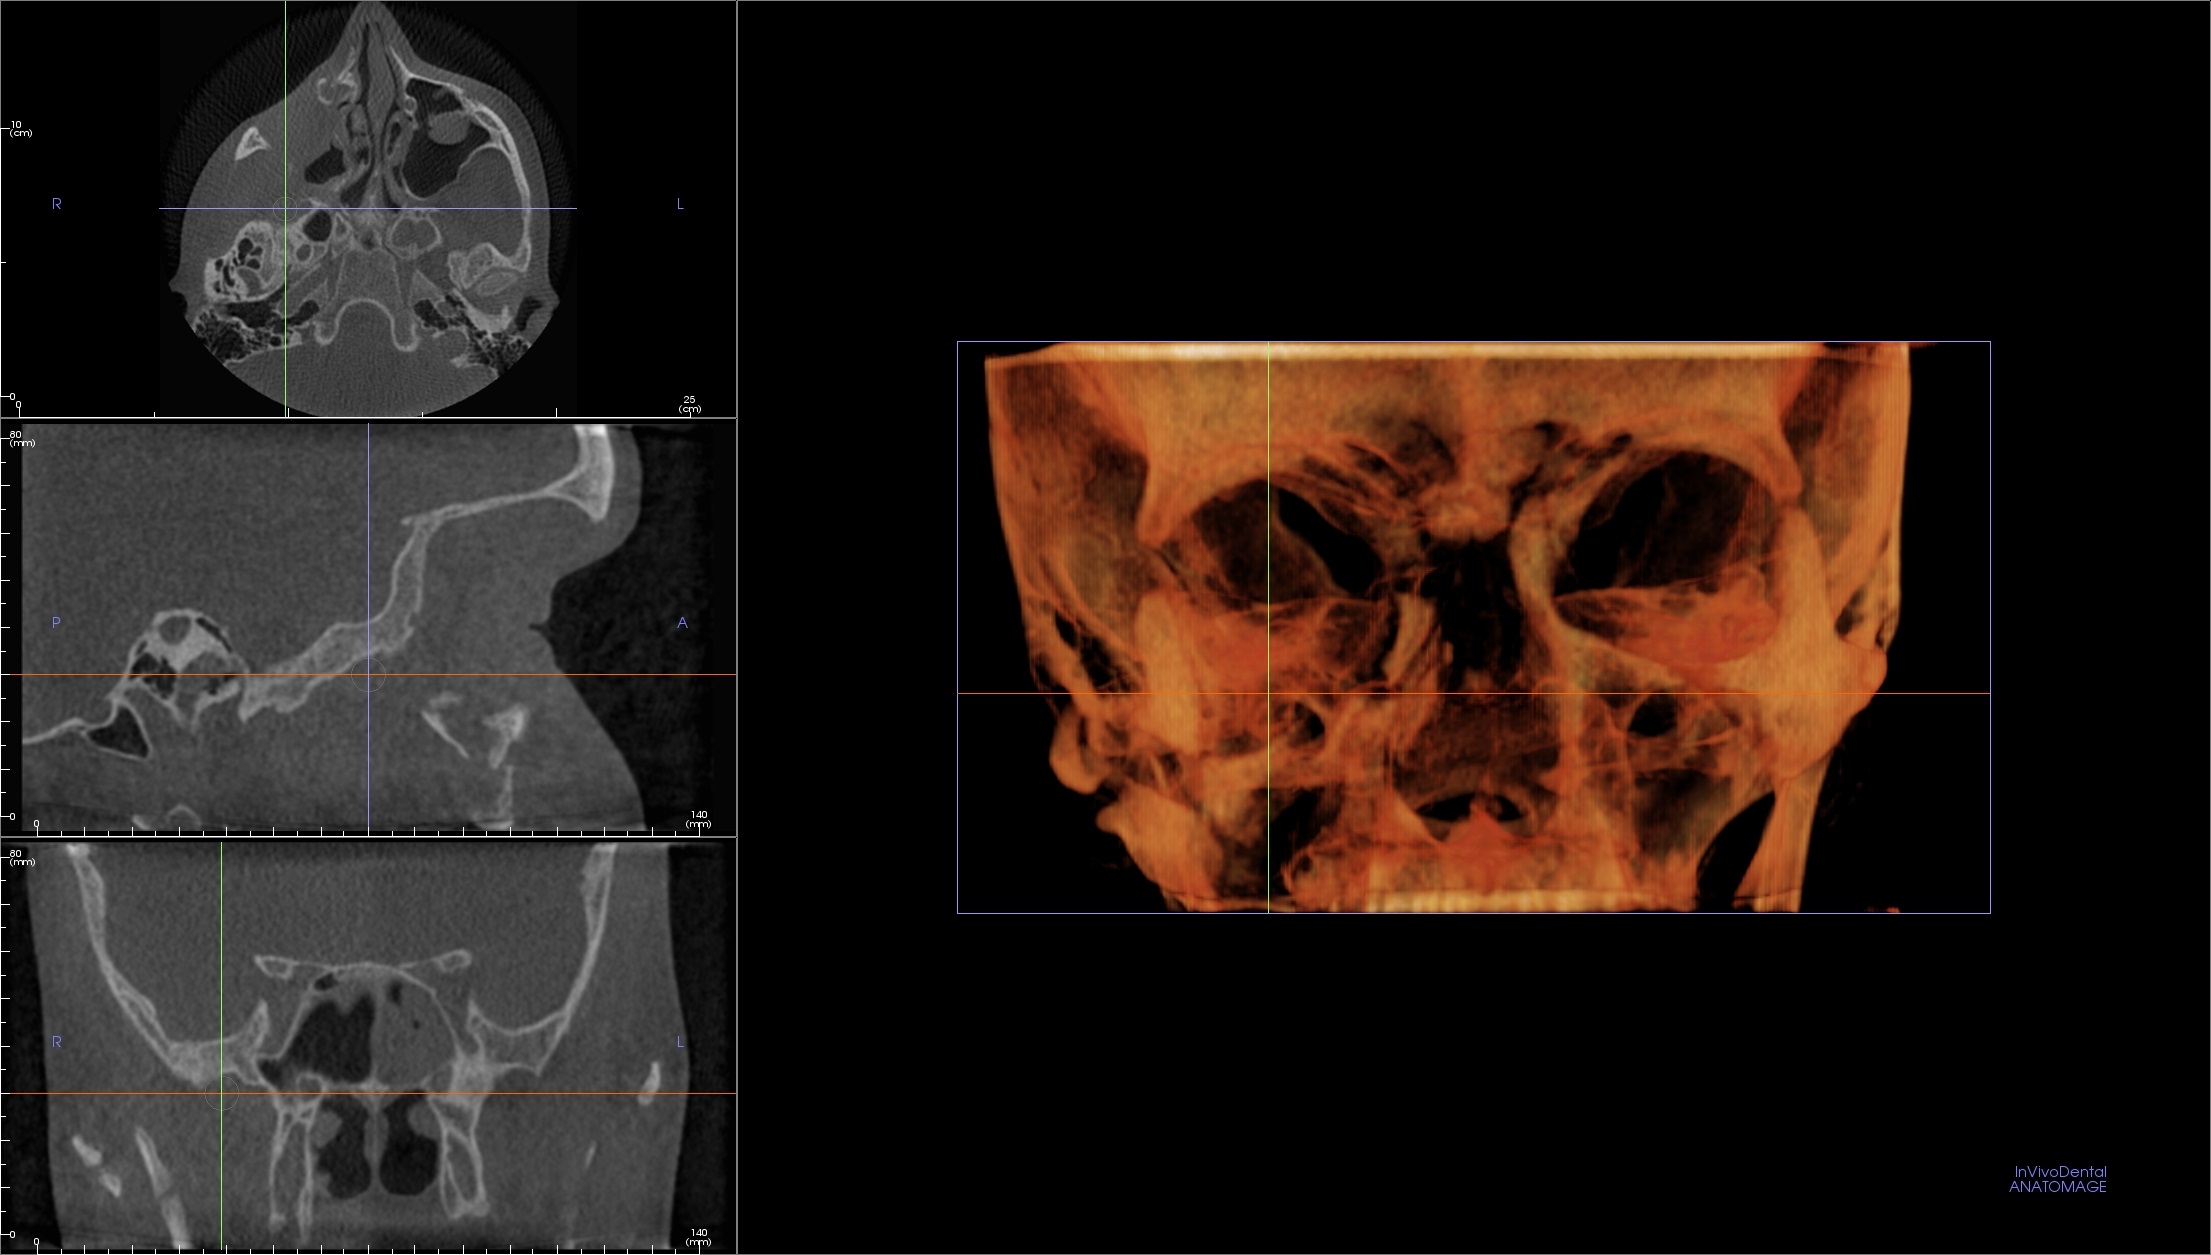

8. Протокол обстеження придаткових пазух носа.

Дослідження придаткових пазух носа з розширенням (розміром вокселя) – 0,3 мм, ефективна еквівалентна доза опромінення при дослідженні – 25 мкЗв.

Клінічний випадок – гострий правобічний риносинусит, ретенційна кіста лівого верхньощелепного синусу, викривлення носової перегородки в області переднього кінця середньої носової раковини, зуби верхньої щелепи інтактні.

Мультипланарні зрізи демонструють 100% втрату повітряності правого верхньощелепного синуса, поширення тіні в середній та нижній носовий хід, середню групу клітин гратчастого лабіринту і частково в дно правої лобної пазухи. На тлі зміненої слизової визначаються поодинокі дрібні бульбашки повітря, що є ознакою гострого процесу. Остіомеатальний комплекс праворуч затінений. Всі кісткові структури без ознак деструкції.